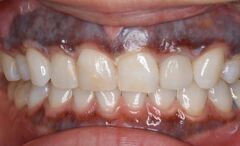

歯は削れば削るほど、もろくなります。歯の表面のエナメル質に無数のひびが入ったり、インレー(歯の詰め物)

(虫歯よりもかなり大きく削る)を装着すると、くさびのような働きをして、歯が割れてしまう事があります。

●大きく削ってインレーを詰めても細菌の取り残しがある→数年後、虫歯の再発

●大きく削ることで、別の痛みが引き起こされる場合がある

●削った部分がむき出しのまま、うがいをさせる。唾液で汚染される→さらなる虫歯や神経の炎症を起こす